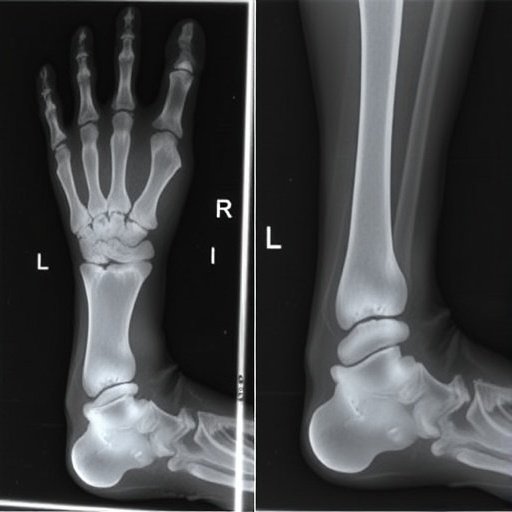

The gorilla lip sign is characterized by a specific presentation of the lateral aspect of the foot in the AP view of radiographs. When interpreted correctly, it serves as a powerful visual cue, allowing radiologists to diagnose talocalcaneal coalition effectively. This study emphasizes the importance of recognizing classic signs in radiology that can directly impact patient management and outcomes. For radiologists and orthopedic specialists, this newfound knowledge reiterates the critical role of advanced imaging techniques in evaluating structural abnormalities in children.

Anteroposterior radiographs are a standard imaging modality in pediatric practice due to their accessibility, non-invasiveness, and the wealth of information they can provide. However, interpreting these films requires a keen eye for detail. The gorilla lip sign stands out as a particularly reliable indicator, setting the groundwork for further exploration into other potential markers that could enhance diagnostic efficacy. The researchers meticulously analyzed numerous AP radiographs, documenting the presence of the gorilla lip sign in a series of pediatric patients diagnosed with talocalcaneal coalition.